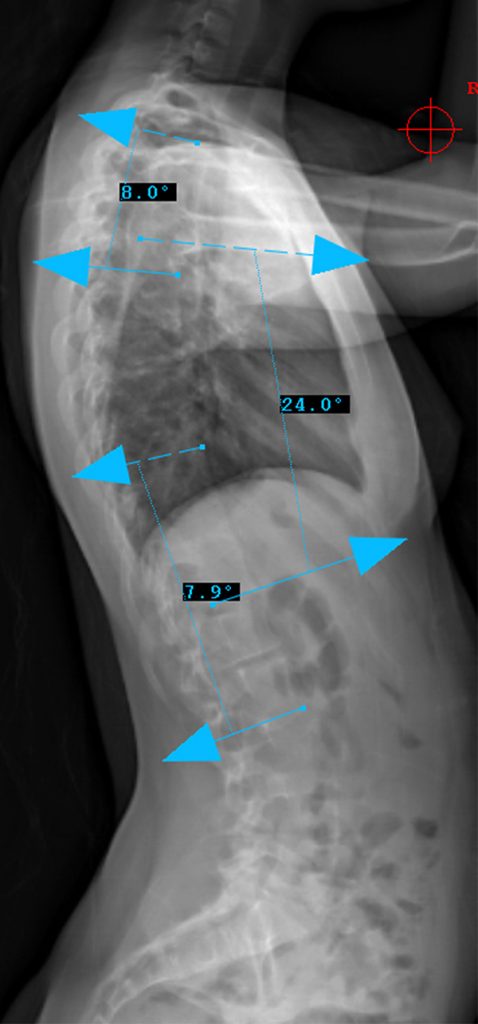

Preop RIGHT Bend

Lenke Type V describes a major curve in the thoracolumbar/lumbar region. The apex of the greatest coronal plane deformity is between T12 and L4. The main thoracic curve is non-structural with a side-bending Cobb of less than 25 degrees and a T10-L2 kyphosis of less than 20 degrees. All of these curves have a “C” lumbar spine modifier. The three sagittal modifiers are still applicable. These curves may be treated with either an anterior or posterior spinal fusion. The fusion levels are often the upper and lower end-vertebrae of the coronal plane deformity. For successful selective fusion of the thoracolumbar/lumbar spine the Cobb angle, apical vertebral translation, and apical vertebral rotation ratios (ThL/L:MT) should be greater than 1.25. In addition the MT curve should be flexible without evidence of thoracolumbar junctional kyphosis (T10-L2 > 20 degrees).